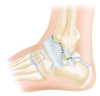

• O que consiste o tratamento cirúrgico pela técnica de Brostrom para instabilidade recorrente?

A

• Reparo do ligamento talofibular anterior + calcaneofibular

• Sutura direta dos ligamentos rompidos (mesmo crônico)

• Bom resultado pós operatório → ganho de ADM, tilt talar e boa resistência mecânica

# Instabilidade do tornozelo - O que consiste o tratamento cirúrgico pela técnica de **Brostrom - Gould** para instabilidade recorrente?

- **Reforço do retináculo dos extensores após reparo talofibular anterior + calcaneofibular** - Bom para pacientes com instabilidade + necessidade de ADM ampla